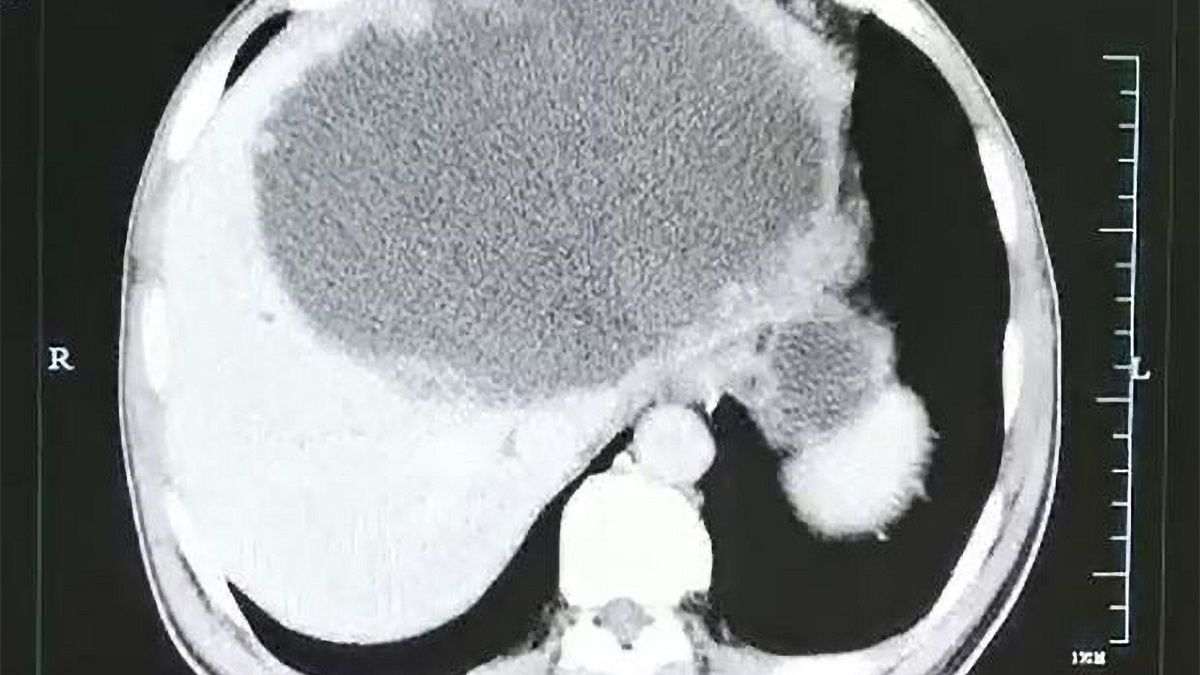

Kiedy lekarze z First People's Hospital w Hangzhou w Chinach w końcu wykonali mężczyźnie tomografię komputerową, byli mocno zdziwieni. Wykazała ona ropień o długości 19 cm oraz szerokości 18 cm w lewym płacie wątroby pacjenta. Poza tym na ścianach ropnia zaczęły rosnąć guzy.

Początkowo lekarze usunęli mężczyźnie ropień. Jednak trzy tygodnie po operacji na wątrobie wciąż były widoczne zmiany.

Ropień na wątrobie

Ropień na wątrobie © East News